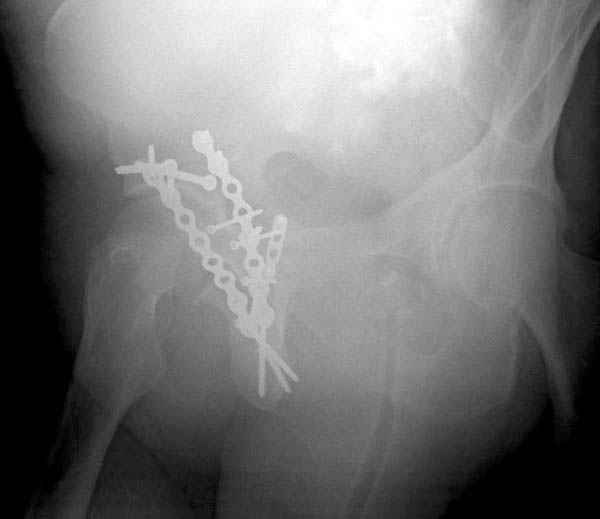

Дополнительно имеется перелом ацетабулума: задняя

колонна с полупоперечным переломом, и переломы костей лица.

На седьмой день зафиксирован перелом ацетабулума через задний доступ. Перед операцией для профилактики DVT, IVC фильтер, также получает Lovenox.

Извиняюсь за качества снимков, обычный больной в 300 фунтов, портативным ренген аппаратом не пробить.